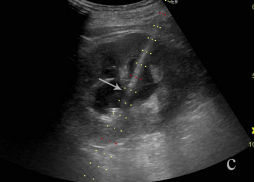

胆管穿刺置管-                                                                                                                         a超声引导胆管穿刺置管引流              b 超声引导胆囊穿刺置管引流                 c超声引导肾盂穿刺置管引流